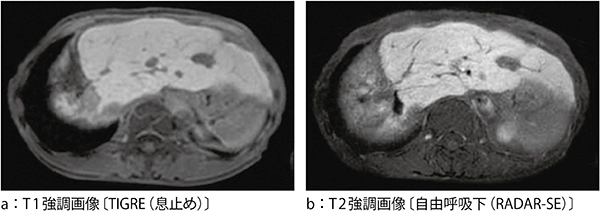

図5に,呼吸同期とRADARによる腹部の画像例を示す。RADARを用いることで,自由呼吸下においても同等の画質を得ることができている。また,図6に,Gd-EOB-DTPAを適用した臨床例におけるTIGRE息止め画像とRADAR-SE画像を示す。RADAR-SEでは自由呼吸下にて,より空間分解能の高い画質が得られている。

図6 Gd-EOB-DTPA臨床画像例